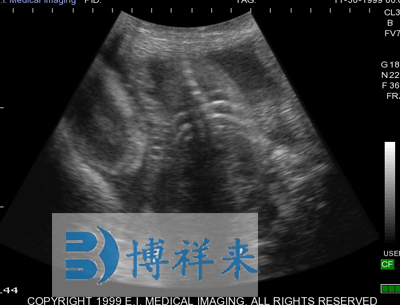

使用对象:牛、马等动物

| 尺寸和重量 | Ibex Lite:IP56 -黄色;8.9”L,7”W,2.2”D;3.61磅(1.63Kg) | 应用范围 | 牛,马,宠物,猪,珍惜动物和小反刍动物等 |

可换探头,可配备:128振元(5-8MHZ)直肠探头、128振元凸阵(2.5-5MHZ)直肠探头、128振元微凸探头以及特殊探头、支持3.5兆赫至7.5 MHz扇形探头等 支持用户可选择探头扫描方向 |

| 超声类型 | 数字超声 | 产科软件 | 各种动物妊娠期参数表格 |